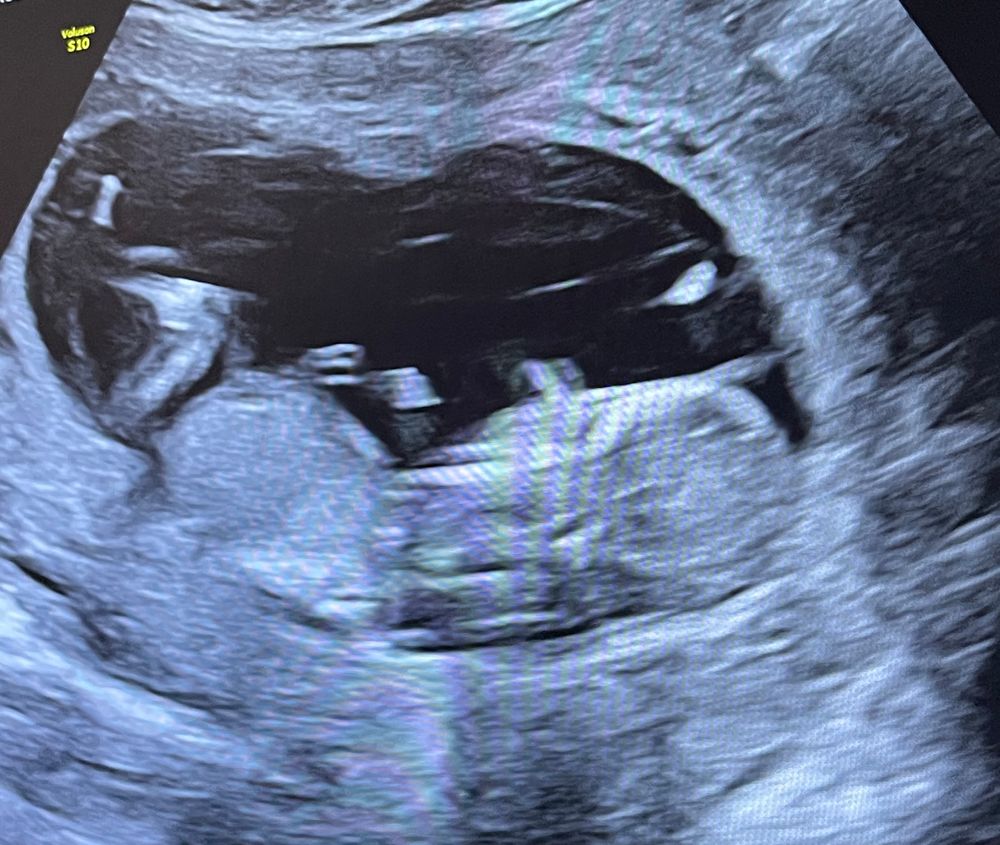

Тут не видно, половой бугорок на этом снимке узи не просматривается

Айсо, ну здравствуйте! Каким образом его может быть видно сквозь ноги? У вас же ребёнок не прозрачный 😄Это просто тень на снимке, но точно не половой бугорок)

Айсо, посмотрела, но тоже нет того ракурса на снимка, ребёнок прячет всё. Потерпите немного, скоро всё узнаете)

Но если нет сил терпеть до 2 скрининга, можно сходить платно на узи по определению пола)